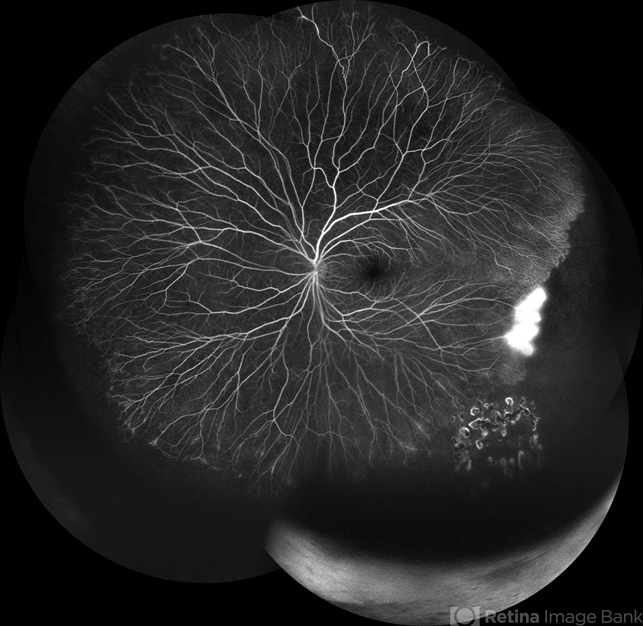

- familial exudative vitreoretinopathy (FEVR), fluorescein angiogram (FA)

- Widefield FA montage of LE of a 13 year old male, showing leakages and capillary non-perfusion areas , in a case of Stage 1 Familial Exudative Vitreoretinopathy